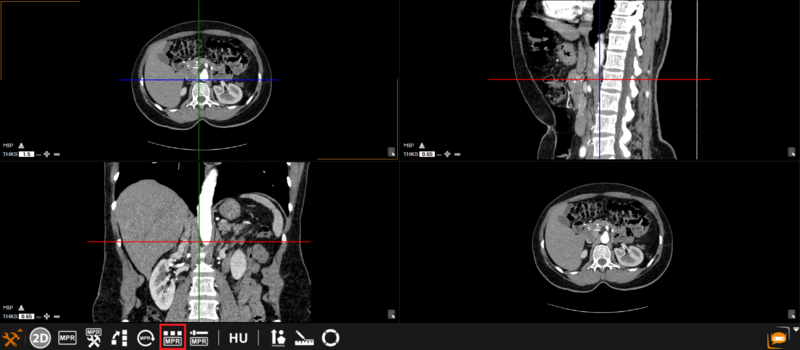

The user can choose from any of these predefined viewing protocols within the MPR mode:

Here are the different viewing protocols you can choose from: